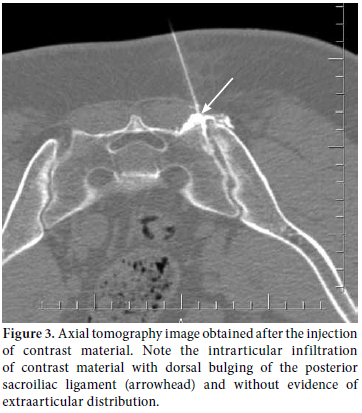

All injections were performed by one of the authors at an outpatient clinic according to the technique previously described by Bollow et al.[16] The patients were placed in a comfortable prone position on the CT table. After scouting the pelvis, the SIJs were scanned with a section thickness of 4 mm and a table advancement of 8 mm while being viewed in the bone window on a Somatom plus CT scanner (Siemens AG, Munich, Germany). The section position with the most suitable access to the synovial articular compartment[17] on both sides was set as the table position (Figure 1). After positioning the table, the definitive gluteal injection sites on one or both sides were indicated on the skin with a grease pencil, and the injection area was disinfected and draped with sterile cloths. After local anesthesia (10 ml of 2% lidocaine per joint), the Chiba needle tip (1.2 mm diameter=18 gauge, 50 to 100 mm length; Angiomed Germany, Karlsruhe, Germany) was positioned in the articular cavity and controlled by CT (Figure 2a, b). Then the joint space was confirmed by at least 3 mls of nonionic contrast medium (Ioversol, Optiray, Covidien, Mansfield, MA, USA) injection (Figure 3). Finally, 0.5 ml of 10% hypertonic saline was injected into the space for the pain provocation test. This test was considered positive when it provoked the same pain as the patient’s symptoms.[11] After the provocation test, a mixture of long-term corticosteroid (80 mg triamcinolone acetonide, Sinokort-A, IE, İstanbul, Turkey) and local anesthetic (4 cc levobupivocaine hydrochoride, Chirocaine, Abbott Laboratories, Abbott Park, Illinois USA) was injected, and the injection site was closed. After injection, no additional medications, including anti-inflammatory drugs, were prescribed for any patients in order to prevent any bias of pain evaluation. The patients were strictly informed about the clinical follow-up period and meticulously controlled.